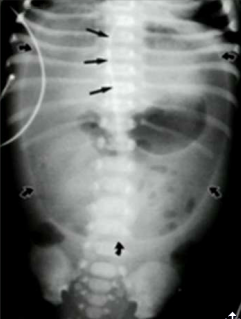

What sign is this?

Rigler sign, air on the inside and outside of the body, indicating pneumoperitoneum.

Football sign indicating pneumoperitoneum

Inverted V sign, indicating pneumoperitoneum